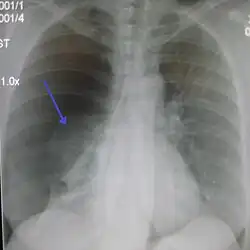

Chest X-ray

A plain chest radiograph, ideally with the X-ray beams being projected from the back (posteroanterior, or "PA"), and during maximal inspiration (holding one's breath), is the most appropriate first investigation.[35] It is not believed that routinely taking images during expiration would confer any benefit.[36] Still, they may be useful in the detection of a pneumothorax when clinical suspicion is high but yet an inspiratory radiograph appears normal.[37] Also, if the PA X-ray does not show a pneumothorax but there is a strong suspicion of one, lateral X-rays (with beams projecting from the side) may be performed, but this is not routine practice.[18][22]

Anteroposterior inspired X-ray, showing subtle left-sided pneumothorax caused by port insertion -

Lateral inspired X-ray at the same time, more clearly showing the pneumothorax posteriorly in this case -

Anteroposterior expired X-ray at the same time, more clearly showing the pneumothorax in this case -

Chest X-ray showing a pneumothorax on the right (left in the image), where the absence of lung markings indicates that there is free air inside the chest -

Chest X-ray showing the features of pneumothorax on the left side of the person (right in image)